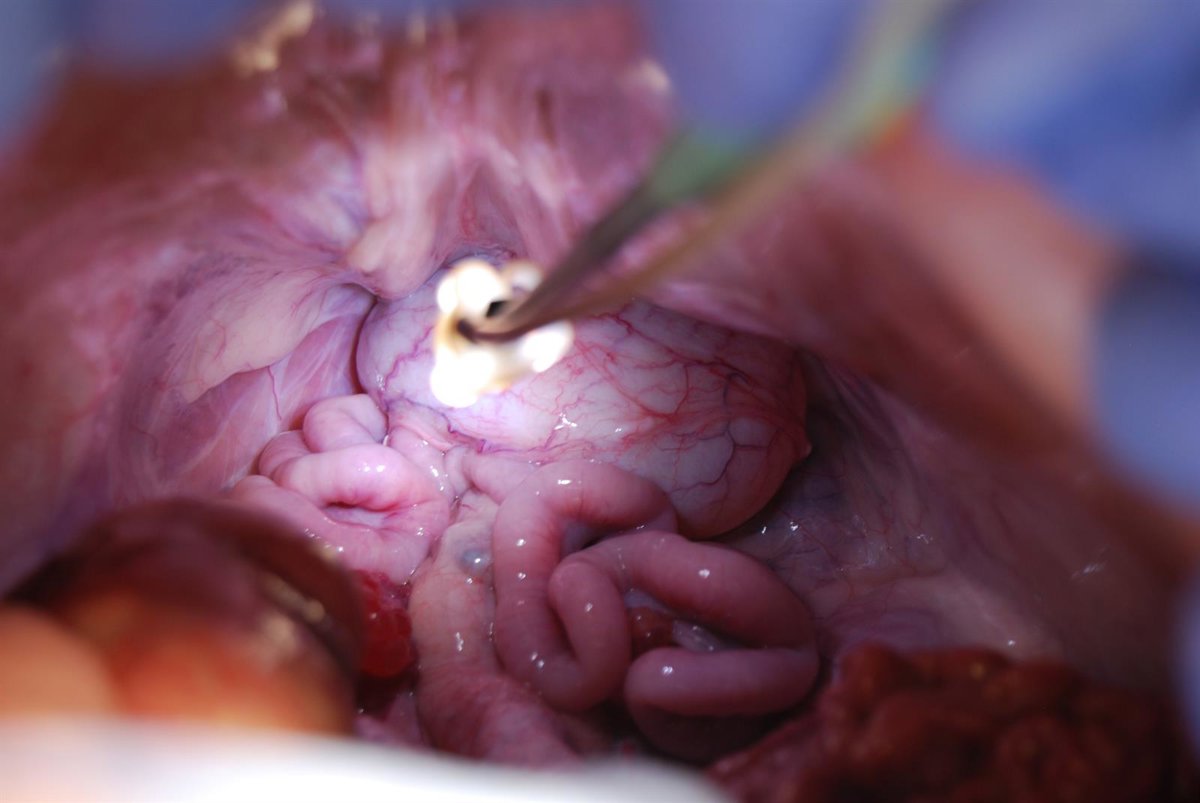

Una operación con el dispositivo Rutilight del Hosp.Germans Trias i Pujol

Bautizado como Rutilight, el sistema de iluminación --desarrollado a través de la 'spin-off' Swan Medical-- permite acercar más la luz que en los sistemas tradicionales y ponerla donde se necesita para trabajar, lo que "facilita la labor de los cirujanos y permite afrontar y resolver eventuales complicaciones", han añadido.

El dispositivo, estéril y de un solo uso, se acopla a cualquier instrumento de entre 5 y 12 milímetros de diámetro, como si se tratara del adaptador para bolígrafo de un compás de dibujo, porque está fabricado con una silicona elástica que le permite ajustarse.

Por ejemplo, puede colocarse en un bisturí tradicional o eléctrico, unas pinzas, un aspirador, unas tijeras o una sonda, y un anillo de leds proporciona la luz y la centra en el punto de trabajo, y puede ser útil para especialidades diferentes, como cirugía general y digestiva, torácica, ginecología, cirugía pediátrica, patología mamaria, traumatología, urología y cirugía plástica, entre otras.